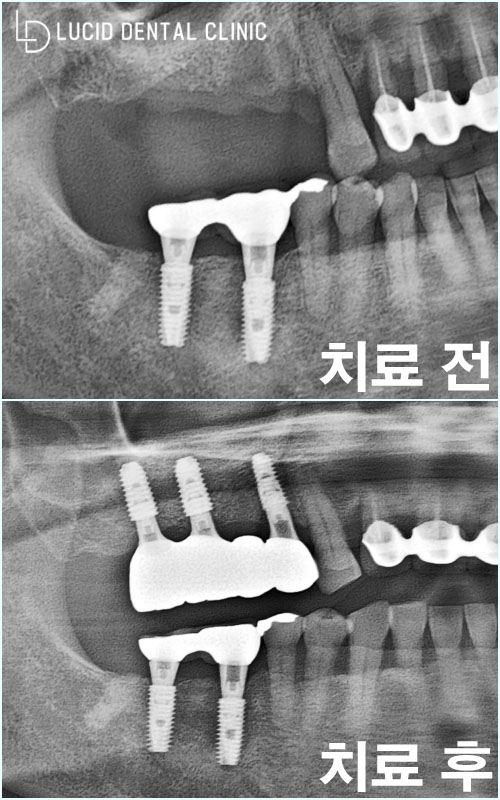

- 어금니 임플란트 수술 완료

파노라마 엑스레이 사진을 통해

환자의 구강 환경을 살펴봤습니다.

소실되었던 어금니의 역할과

심미성까지 온전히 되찾아 드리며

고민을 해결해 드릴 수 있었습니다 :)

환자분께서 수술 이후 꾸준히 논현역 치과 에

내원하시며 관리받으신 덕분인지 예상 날짜보다

훨씬 빠르게 회복되신 케이스라 ㅎㅎ

금방 크라운 보철 장착하고

치료를 마무리 한 기억이 있네요